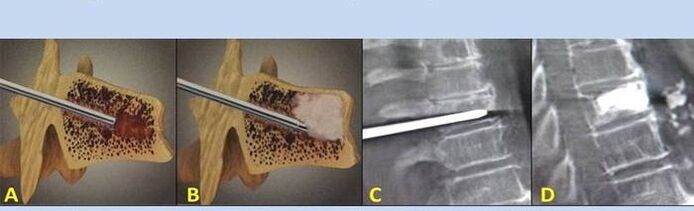

- Nukleoplastika – odstranění jádra meziobratlové ploténky. Operace zmírňuje tlak na nervová zakončení.

- Punkční vertebroplastika – metoda stabilizace obratlů. Během procedury lékař vyplní dutiny páteře kostním cementem.